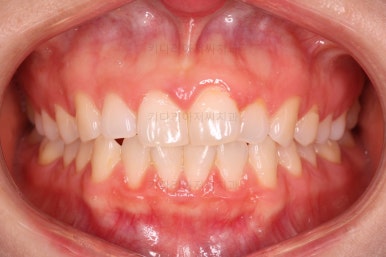

왼쪽 사진들이 부산나비앞니교정 치료 전 모습, 오른쪽 사진들이 치료 후의 모습입니다.

가지런해진 느낌이 전후 비교해보니 훨씬 느껴지실 거에요.